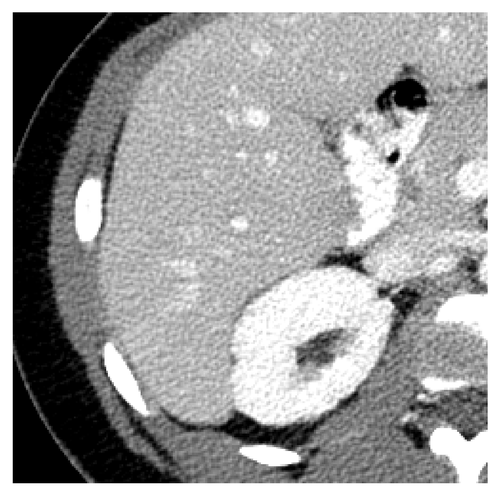

Fig. 9 and 10 show results for Exam 2, a low-contrast clinical exam. Both the full slice and zoomed views show that TMGAN produces a uniform texture for this low-contrast exam, while WGAN-VGG produces a uniform but coarser texture. More importantly, the arrows in Fig. 9(9) and 10(10) show that low-contrast features are best detected using the TMGAN-blended results.